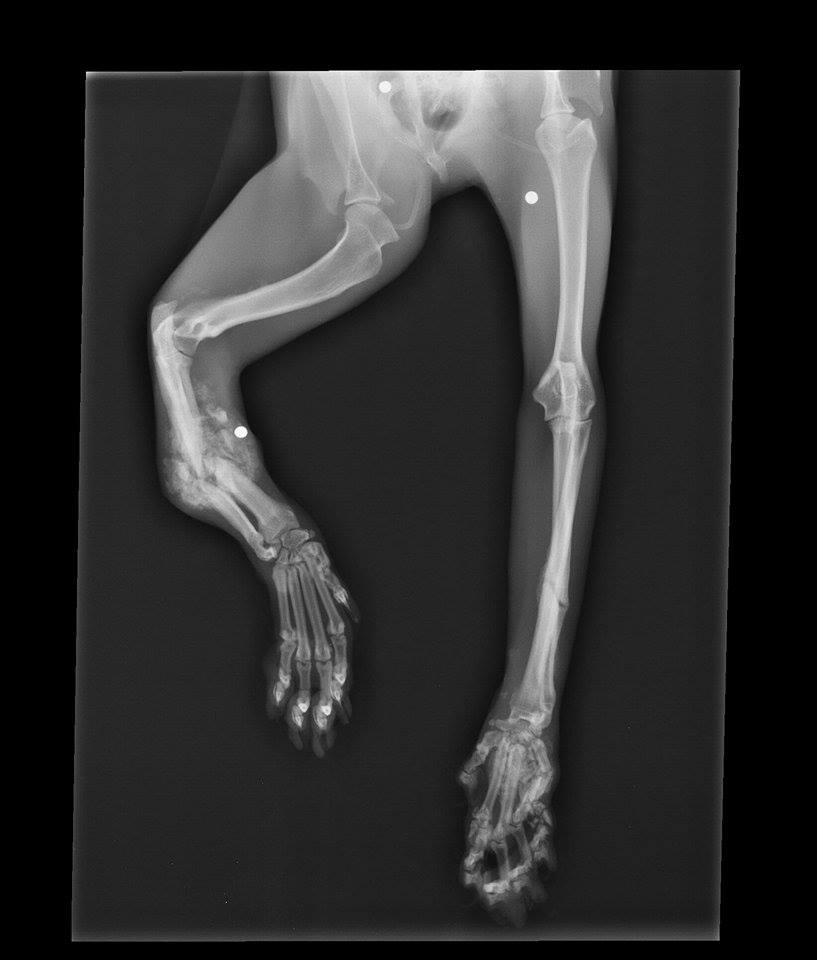

The next day, Copper's appointment at Adrian Animal Clinic revealed the extent of his injuries. X-rays were taken to view the damage and we couldn't believe our eyes. Both paws had several severe fractures and his front left paw had been crushed to point of no return. To make matters worse, x-rays also revealed three BBs or bird shot within his front legs as well. We still had no clue what caused this much damage, but it was beginning to look intentional. Our hearts broke for this poor beautiful, sweet creature.

Upon examination, the veterinarian revealed the bad news. Because of the severity of all of Copper's fractures, treatment through splinting or amputation didn't appear to be viable options. Humane euthanasia was recommended because a quality life did not seem possible with this kind of damage.